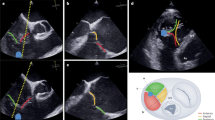

CT parameters are presented in Table 2 and shown in Fig. 2. Right ventricular and atrial volumes were increased in the PA compared to the T-TEER group, but these differences did not reach statistical significance. This was consistent with a more pronounced tenting in PA patients, including the tenting angle of the septal leaflet, which was significantly larger in the PA compared to the T-TEER group. The tricuspid valve area and diameters did not differ significantly between the two groups. The distance between the tricuspid annulus and the RCA was larger in patients who underwent PA compared to T-TEER with a significant difference in segment D8 (Fig. 2). 35 patients in the PA (67%) and 23 patients in the T-TEER group (72%) had at least one segment with a distance to the RCA < 6 mm.

Computed tomography (CT) analysis of right atrial (RA) and right ventricular (RV) height (A), RV length (B), tricuspid annulus (TA) with antero-posterior (AP), septo-lateral (SL), minimal (min) and maximal (max) diameter (C, D), tenting height (E), tenting angle of the anterior leaflet (F), and distance between tricuspid annulus and right coronary artery (RCA, G, H).